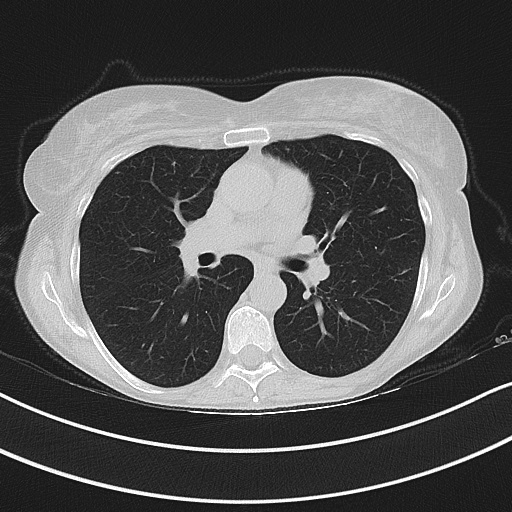

Figure 3 illustrates this further. It presents three cases of unsegmented slices of a CT scan (left column), along with their cases when they are segmented with conventional approaches (middle column) and with our proposed framework SAM2CLIP2SAM (right column). It is evident that the segmentation result with our approach is more accurate and error-prune. In the first case (top row), the mediastinal mass between the left and right lungs is kept when the slices are segmented with conventional approaches, whereas it is not kept (i.e., it is black) when the slices are segmented with our SAM2CLIP2SAM framework. In all cases, one can also note that a bit of the pleural space (e.g. on the peripheral of the lungs) is also kept and is not masked when the slices are segmented with conventional approaches; this is not the case when the slices are segmented with our SAM2CLIP2SAM framework.

Original-Unsegmented Conventionally segmented SAM2CLIP2SAM segmented